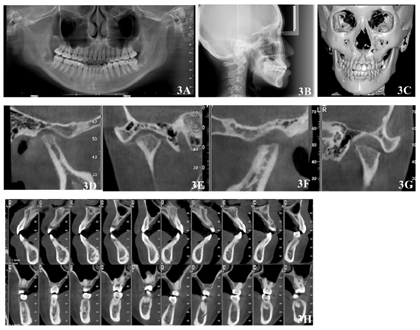

(5)正畸术前X线检查:自然头位下,曲面断层X线片未见明显牙槽骨吸收,未见18、28、38、48。头颅三维重建可见颏部明显右偏。CBCT显示左侧髁突术后断面平整,关节间隙增大;右侧髁突形态不佳,骨皮质连续,关节前、上、后间隙约为1:1:2;各牙根-骨关系未见明显异常。头颅侧位X线片测量数据:SNA角81.8°,SNB角80.6°,ANB角1.2°,FH-MP角36.9°,PP-GoGn角29.8°(图3,表1)。